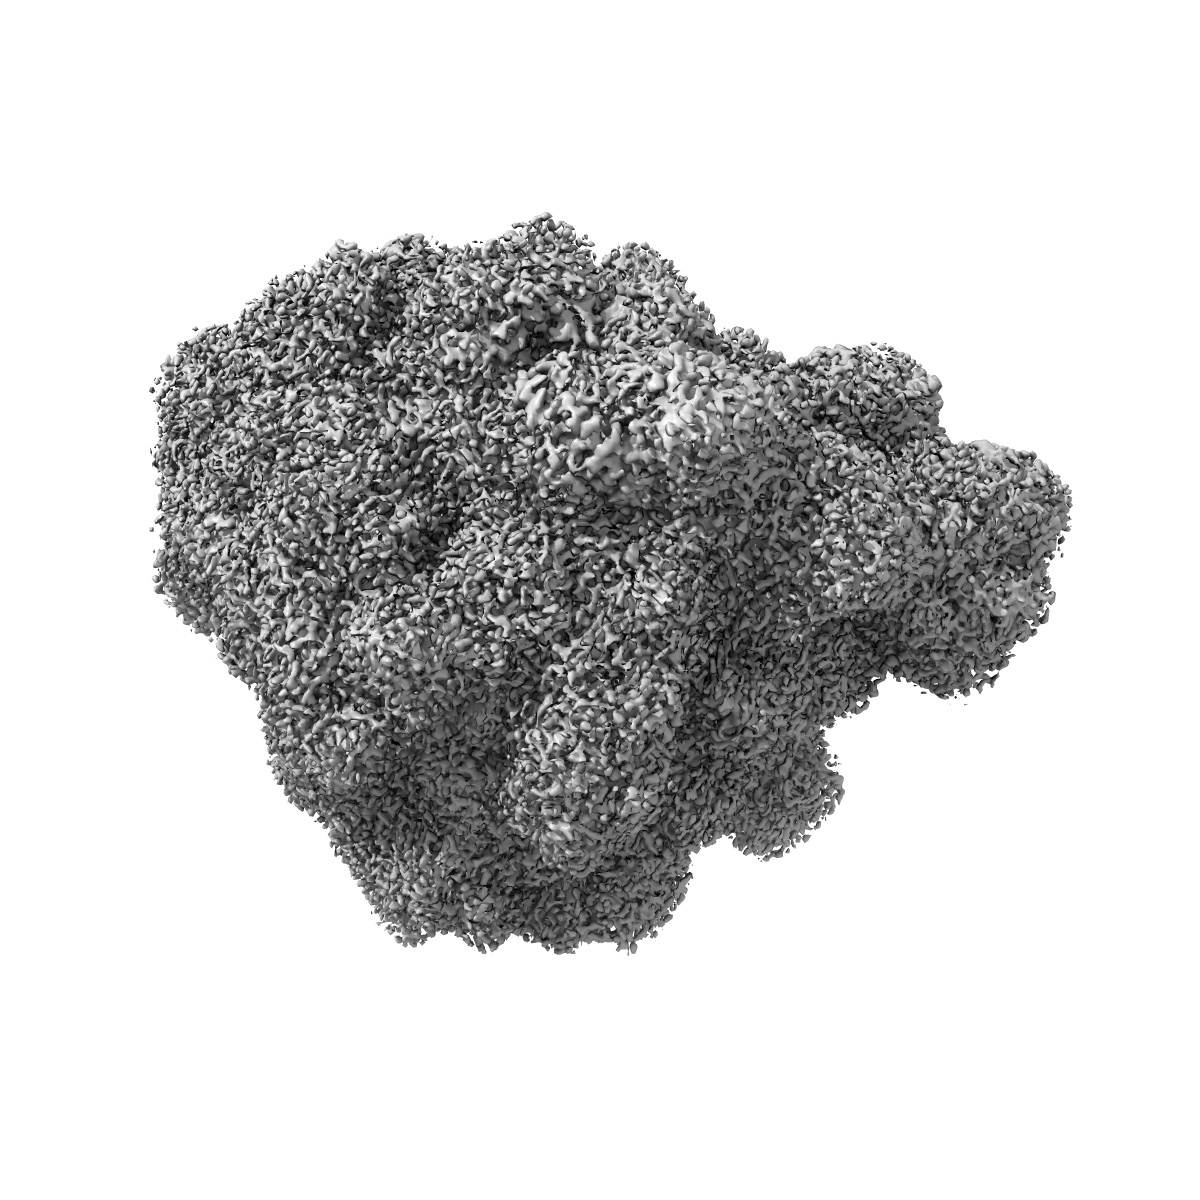

Structure of the 50S subunit of the ribosome from Methicillin Resistant Staphylococcus aureus in complex with the antibiotic, contezolid

Sample Organism: Staphylococcus aureus

Sample: 50S ribosomal subunit

Characterization of the Core Ribosomal Binding Region for the Oxazolidone Family of Antibiotics Using Cryo-EM.

Wright A, Deane-Alder K , Marschall E , Bamert R, Venugopal H , Lithgow T, Lupton DW , Belousoff MJ

(2020) Acs Pharmacol Transl Sci , 3 , 425 - 432